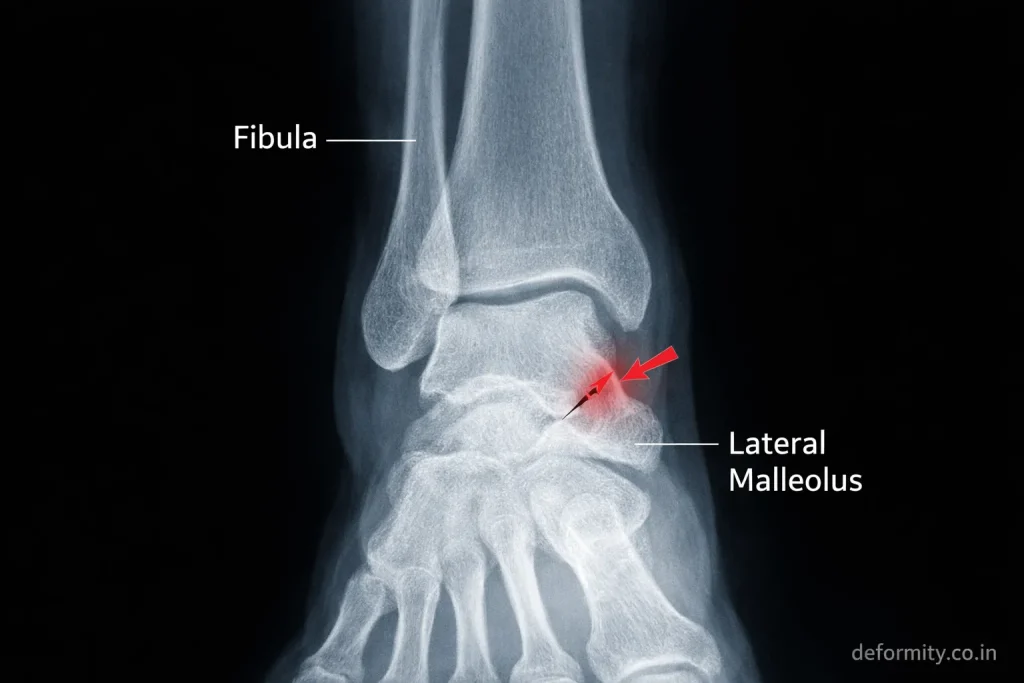

X-ray Imaging

X-rays are the primary diagnostic tool. Standard views include:

- AP view

- Lateral view

- Mortise view

These help identify fracture pattern and displacement.

The lateral malleolus is the bony prominence on the outer side of your ankle. It is the lower end of the fibula and plays a crucial role in stabilizing the ankle joint. A fracture here is often referred to as a distal fibula fracture or outer ankle fracture.